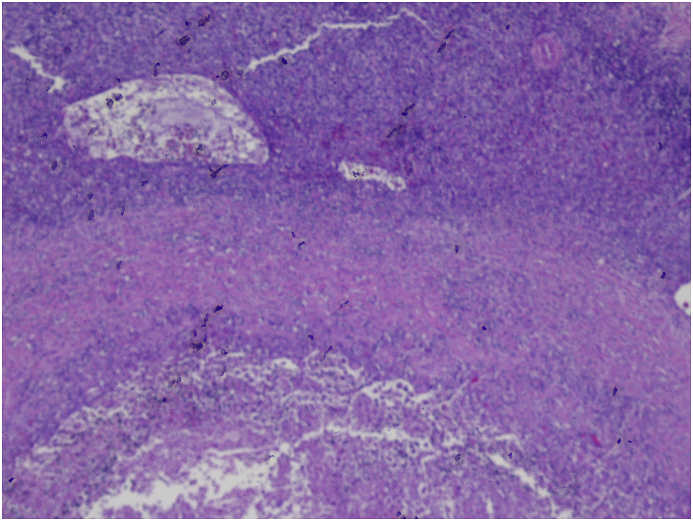

Fig. 5.

H&E stain demonstrating that most of the tumor was necorsed. In this low power image, the outer layer represent thymoma, middle layer shows fibrosis and eventually transitioning to necrosis in the inner most layer.

Fig. 6.

H&E stain, high power field; The large cells with lightly stained nuclei represent epithelial cells (tumor cells) which are interspersed with lymphocytes(cells with large and darkly stained nuclei).

The patient underwent median sternotomy with exploration and complete resection of thymic mass. Pathology confirmed that the mass was truly representing thymoma type B2.